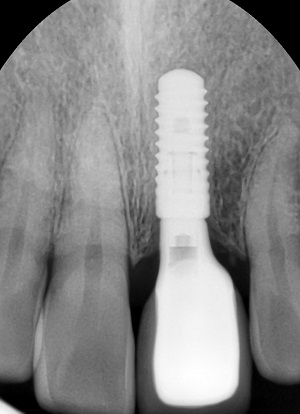

7월 1일부터 임플란트 건강보험 적용이 65세 이상으로 확대되면서 그 수요가 크게 늘 것으로 예상되고 있다. 임플란트는 자연치아를 대체할 수 있어 치아를 상실했을 때 가장 큰 치료 방법이 될 수 있지만 관리가 제대로 이뤄지지 않을 경우 자연치아보다 치주 질환에 노출될 위험이 높아 시술 후 구강관리에 각별히 신경 써야 한다.

임플란트는 자연 치아와는 달리 신경이 존재하지 않아 염증이 생겨도 통증을 잘 느끼지 못할 수 있다. 특히 시술한 잇몸 주위에 염증이 발생되는 질환 ‘임플란트 주위염(periimplantitis)’의 경우 염증 정도에 따라 심한 경우 잇몸뼈까지 녹아내리게 위협하는 질환으로 꼼꼼하고 정확한 치료가 필요하다.

최근 치과 임플란트에서 가장 권위 있는 저널 중 하나인 COIR(Clincal Oral Implant Research)에서 임플란트 시술을 한 후 8년 동안 추적 조사한 결과를 발표했다. 이 논문에 의하면 시술된 임플란트의 60% 넘는 대상에서 ‘임플란트 주위염’이 발생한 것으로 나타났다. (Tenenbaum, Bogen et al. 2016) 이는 일반인들보다 훨씬 높은 수치로서 임플란트의 지속적인 관리가 중요하다는 것을 입증한 결과다.